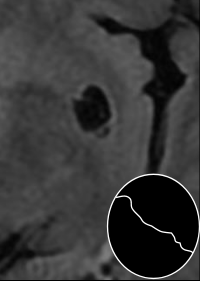

- Dilattion périvasculaire

- Artère au centre

- Souvent dans les noyaux profonds mais peuvent se voir partout